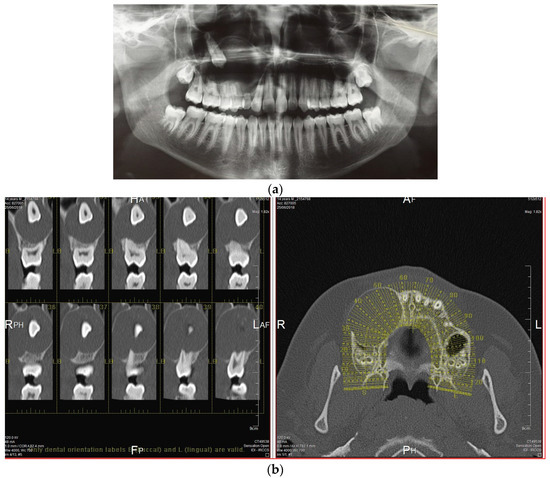

The AOT case refers to 2018 when a 14-year-old male patient was referred to the Department of Oral and Maxillo-Facial Sciences of the Sapienza University of Rome with pain and swelling in the right maxilla. Clinical examinations showed a single 4 × 4 cm swelling on the labial aspect of the right maxillary alveolus in relation to teeth 12 to 17. The overlying mucosa was normal (Figure 1). On palpation, the swelling was bony, hard and non-tender. Radiographic examinations such as panoramic X-ray and computed tomography scan (Figure 2) showed a demarcated unilocular radiolucent lesion extending from 1.2 to 1.7 with a permanent canine embedded within the lesion and pushed away from its normal position. The possibilities of follicular cyst or odontogenic tumor were considered clinically.

Figure 2. Radiographic examinations, such as panoramic X-ray (a) and computed tomography scan (b), reveal a well-defined, single-chambered radiolucent lesion spanning from 1.2 to 1.7, with a permanent canine embedded within the lesion and displaced from its usual position.